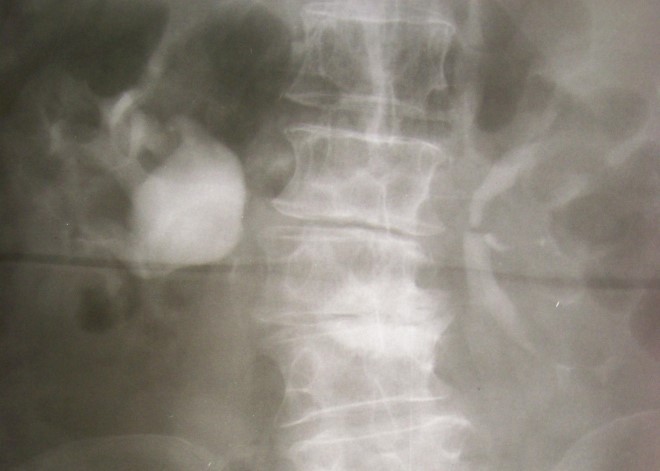

Особенности строения и расположение парных органов почек обуславливает сложную диагностику возможных отклонений. Выявить инородные образования, которые могут развиваться на протяжении жизни или из-за определенных перенесенных заболеваний, в случае с почками затруднено — из-за того, что почки расположены за брюшной полостью. Паренхиматозную кисту почки также практически невозможно заметить, в том числе на УЗИ, до тех пор, пока опухоль не укрупнится до определенных размеров. Паренхиматозная киста левой почки что это такое и чем отличается от опухоли на правой стороне? Этот вопрос интересует многих наших читателей, и далее мы ответим на него со всеми подробностями.

При выявлении малейших симптомов заболевания, а также при появлении признаков проблем с мочеполовой системой, больной обязан немедленно обратиться к доктору. Врач назначит необходимое обследование, УЗ-сканирование органов брюшной полости и определит оптимальное лечение кисты паренхимы правой почки или левой стороны органа.